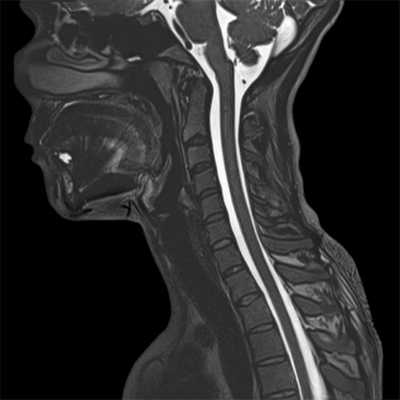

КТ или МРТ шейного отдела позвоночника - что лучше выбрать?

По мнению многих неврологов и травматологов магнитно-резонансная томография (МРТ) шейного отдела позвоночника относится к наиболее информативным методам диагностики заболеваний и повреждений спинного мозга, его корешков и мягкотканных структур позвоночника. У нее есть следующие диагностические преимущества:

- неинвазивность;

- отсутствие лучевой нагрузки;

- трехмерный характер получения изображений;

- отсутствие артефактов от костных тканей;

- высокая дифференцировка мягких тканей.

Недостатком МРТ является большое время, необходимое для получения изображений. В среднем сканирование одной зоны позвоночника занимает 15-20 минут. Данные МР-обследования не дают возможности надежного выявления кальцификатов и некоторых видов патологий костных структур позвонков. Поэтому в случае спинальной травмы, когда нужна быстрая оценка состояния костных структур позвоночника, врачи отдадут предпочтение КТ позвоночника.

Поскольку для хорошей визуализации магнитно-резонансному томографу нужно много клеток с атомами водорода, то ткани с большим содержанием воды лучше всего визуализируются на МРТ снимках. Поэтому МР-томография позвоночника очень хорошо показывает:

- спинной мозг;

- нервные волокна;

- сосудистое русло;

- мягкие ткани (мышцы, сухожилия, связки, межпозвоночные диски).